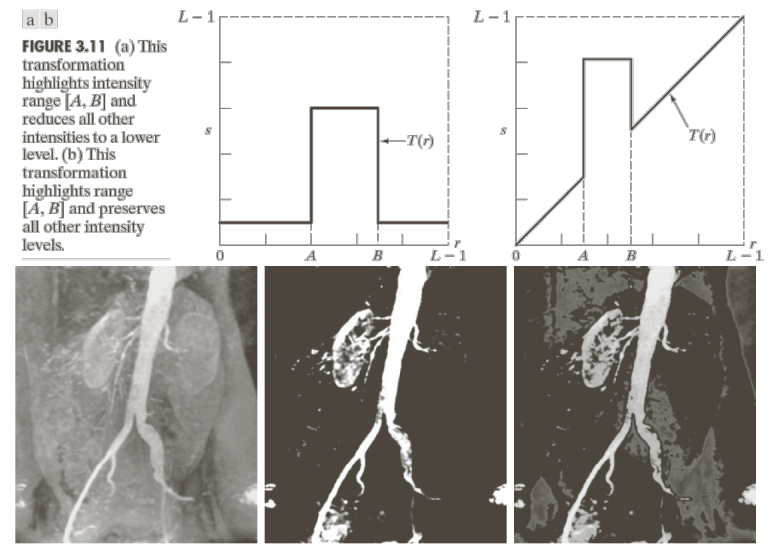

Gray-Level Slicing

특정한 Pixel Value 영역을 기준으로 밝기값을 조절하는 영상 처리 기법이다.

첫번째 그래프는 $A,B$를 제외한 모든 영역의 밝기 값을 0에 가까운 값으로 설정함을 알 수 있다.

반면, 두번째 그래프는 $A,B$를 제외한 모든 영역의 밝기는 유지하면서, 해당 영역은 원본보다 더 밝은 값으로 설정함을 알 수 있다.

우리가 추출하기 원하는 영역, 대상의 밝기 값 분포를 알고 있다면, 해당 영역 제외 모두 0으로 설정하여 원하는 영역만 확인할 수 있다.